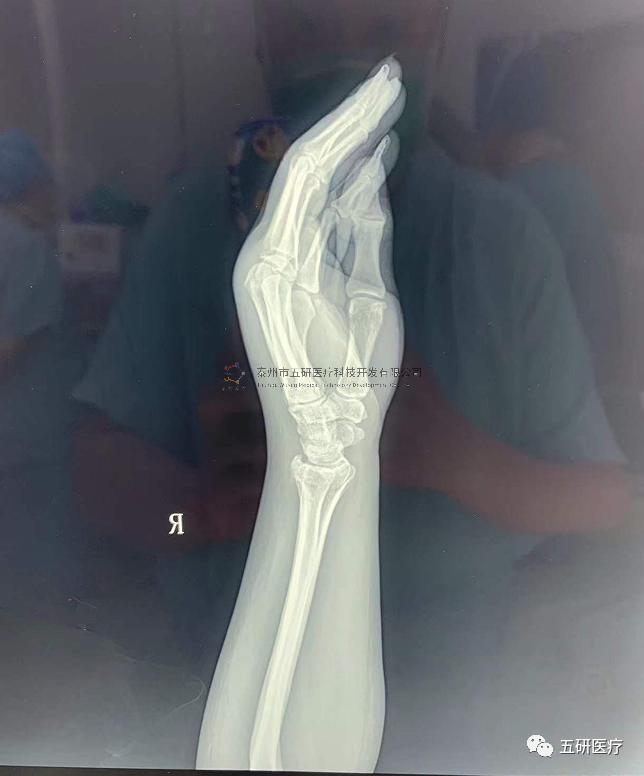

// 腕架

本病例由中國中醫(yī)科學院望京醫(yī)院骨綜科提供(術者:支架醫(yī)生常醫(yī)師)

【基本資料】患者,女,61歲

本病例腕架骨折。術前正側位片:右橈骨遠端骨折。

采用常規(guī)方法固定,自掌骨尺側,約基底稍偏遠處穿入螺紋針。

外架馬蹄環(huán)穿過骨針,更方便調整固定角度。